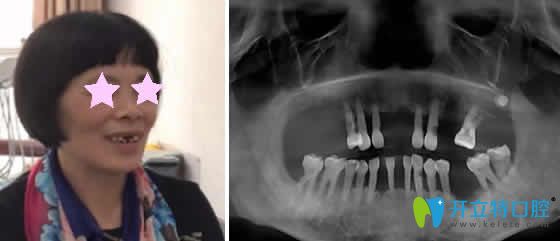

重慶華諾世口腔怎么樣?看李清醫(yī)生微創(chuàng)即刻種植牙案例效果圖:

種植牙前:上邊門牙兩邊牙齒缺失,吃飯困難。

種植牙后:即刻種植牙當(dāng)天回家能啃蘋(píng)果,而且自然美觀。